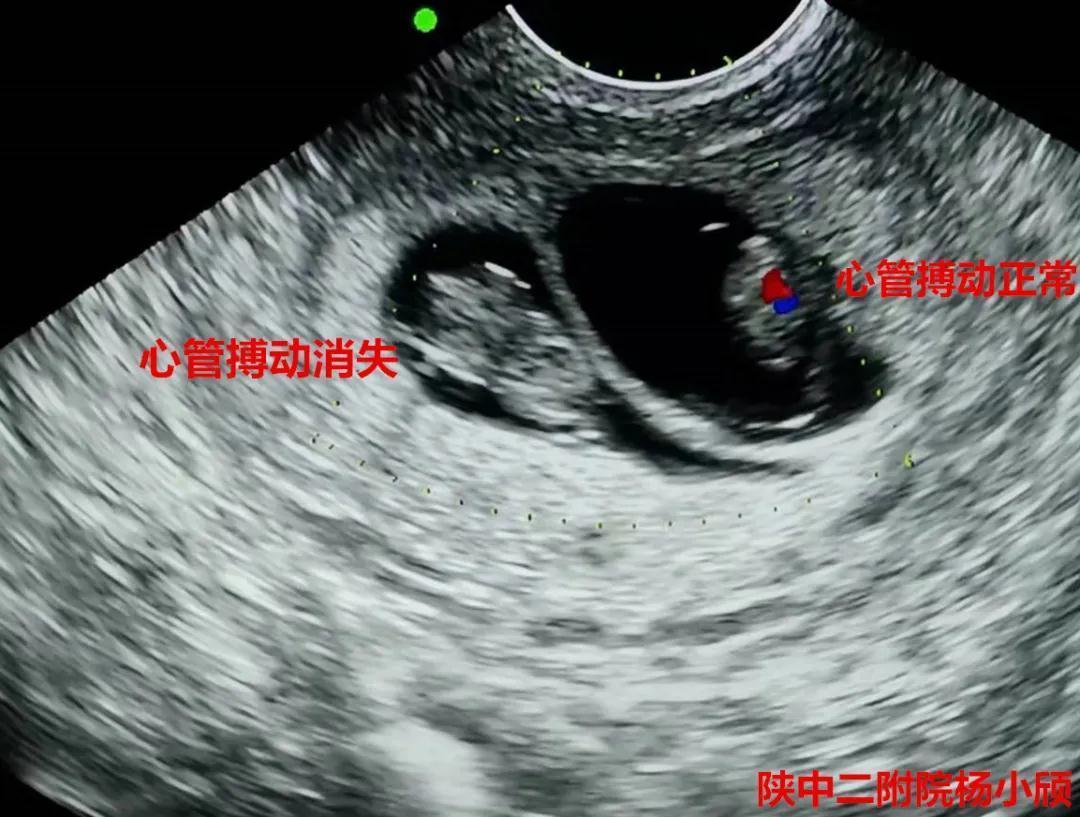

在积极完善术前相关检查,排除手术禁忌症,充分告知患者及家属三胎妊娠的风险,签署知情同意书后,3月20日下午,杨小颀亲自操刀为患者实施了经阴道B超引导下选择性胚胎减灭术。手术顺利完成,病人病情平稳。术后24小时阴超提示,减胎孕囊胎心停止。7天后复查彩超提示,两胚胎存活,一胚胎停止发育。这标志着这台高难度的减胎手术圆满完成,达到预期效果,也再次彰显了陕西中医药大学第二附属医院(西咸新区中心医院)生殖内分泌科在减胎术方面的巨大进步。

术后24小时阴超